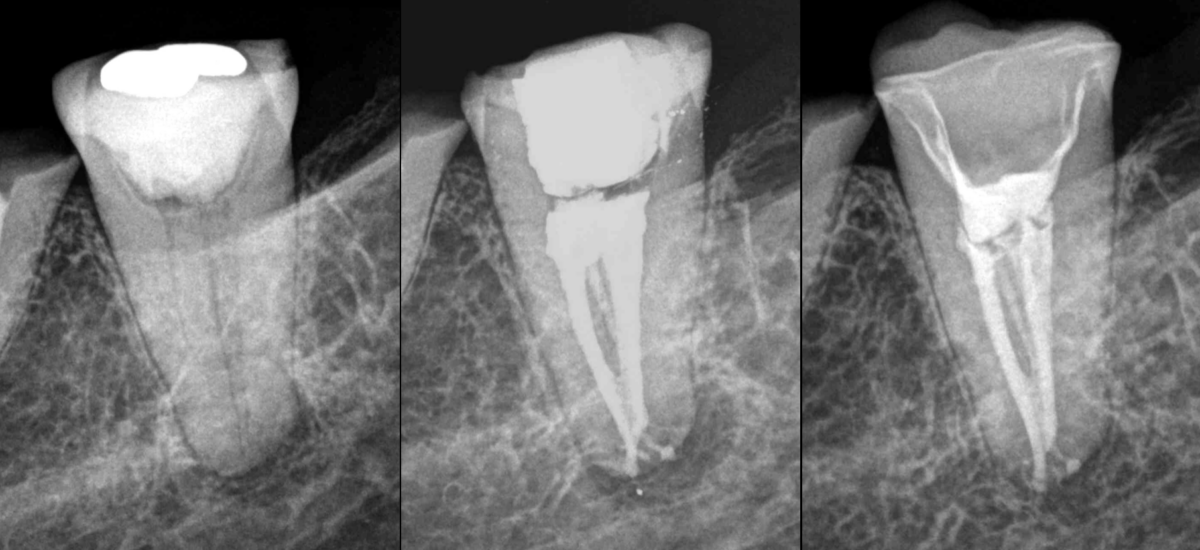

🔍 𝐄𝐭 𝐬𝐢 𝐥𝐞 𝐭𝐫𝐚𝐢𝐭𝐞𝐦𝐞𝐧𝐭 𝐧’𝐚𝐯𝐚𝐢𝐭 𝐩𝐚𝐬 𝐞́𝐭𝐞́ 𝐞𝐟𝐟𝐢𝐜𝐚𝐜𝐞 𝐝𝐚𝐧𝐬 𝐜𝐞 𝐜𝐚𝐬, 𝐪𝐮’𝐚𝐮𝐫𝐢𝐞𝐳–𝐯𝐨𝐮𝐬 𝐩𝐫𝐨𝐩𝐨𝐬𝐞́ 𝐚̀ 𝐯𝐨𝐭𝐫𝐞 𝐩𝐚𝐭𝐢𝐞𝐧𝐭𝐞 ?

➡️ De notre côté, il avait été abordé avec la patiente la possibilité qu’une extraction-réimplantation soit réalisée le cas échéant.